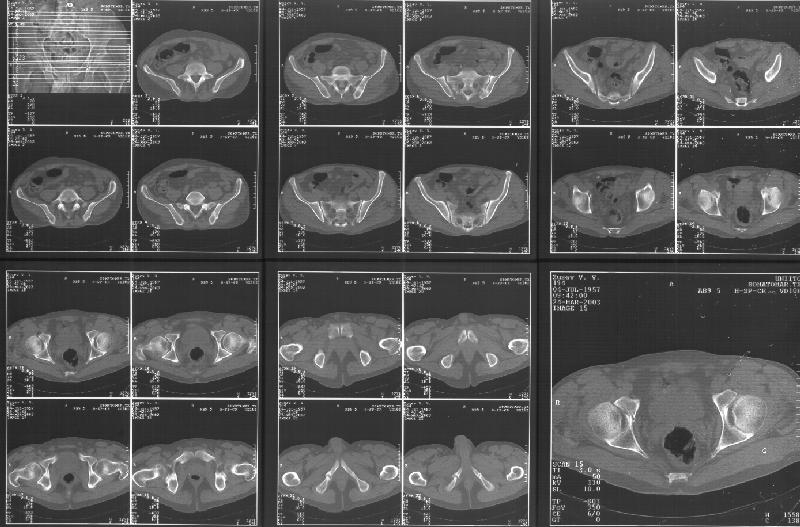

Прилагаю свежую КТ таза.

Картинки см. ниже, левая - с экранным разрешением, вторая - полноразмерная, ~900 кб.

Based on the CT images you provided, he appears to have a nonunion of the the right ischium, which would explain his symptoms. General principles of treatment of hypertrophic (which this appears to be) nonunions suggest rigid fixation, but I'm not sure what the best approach would be. Could get a lag screw across the fracture through a Kocher-Langenbeck approach or plate osteosynthesis through direct ischial approach, but perhaps Chip, Adam or someone with more pelvic fracture experience could enlighten us all.

I think the CT cuts in question are on the right of the bottom row i.e.

http://www.hwbf.org/hwb/conf/alex47/image3a.jpg

Thanks for the link to the plain films and CT images.

I think this is just a pelvic ring disruption that has gone on to a non-union. The arrow is pointing to the inferior ramus non-union, and

the sup ramus is a high "root" fracture, right near the pecten. The sup ramus fracture enters the tab - you could call it an acetabular

fracture - but down here in Dallas we treat these acutely as stable pelvic ring injuries. The fracture in the anterior portion of the

acetabulum is so low it doesn't seem to cause much trouble.

His R sacroiliac joint is opened anteriorly a little bit - the "unreduced posterior lesion" Alex mentioned in his first post. My earlier post about plating, bone grafting, etc., is all wrong.

What you have is a pelvic fracture that hasn't healed after 4 months or so, with a minimal deformity.

I think what I would offer the guy is a percutaneous iliosacral screw to stabilize and improve the SI joint alignment, coupled with a perc anterior column screw to stabilize the high ramus fx. These screws aren't easy to place, and have a host of potential problems and complications. But, I think they would work.

Как Вы сами видели на томограммах, грубых деструктивных явлений крестцово-подвздошного сочленения не определяется( маркировка правая -левая сторона не видна), определяется сравнительно незначительное расширение суставной щели с одной стороны и не более того.

Виноват, первый раз не обратил внимания на возможность полноформатного просмотра томограмм. В этой связи -дополнения к своему первому комментарию: сросшийся перелом вертлужной впадины справа, L5-S1 спондилоартроз, расширение суставной щели крестцово-подвдзошного сочленения справа может компрометировать его стабильность и вызывать локальные боли, но вряд ли это может давать двусторонние проявления в нижних конечностях. Все-таки миелограмма или ЯМР желательно иметь, чтобы определиться в тактике.